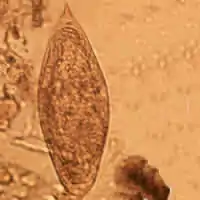

Schistosoma mansoni egg

Thirteen species are found in Africa. Twelve of these are divided into two groups—those with a lateral spine on the egg (mansoni group) and those with a terminal spine (haematobium group).